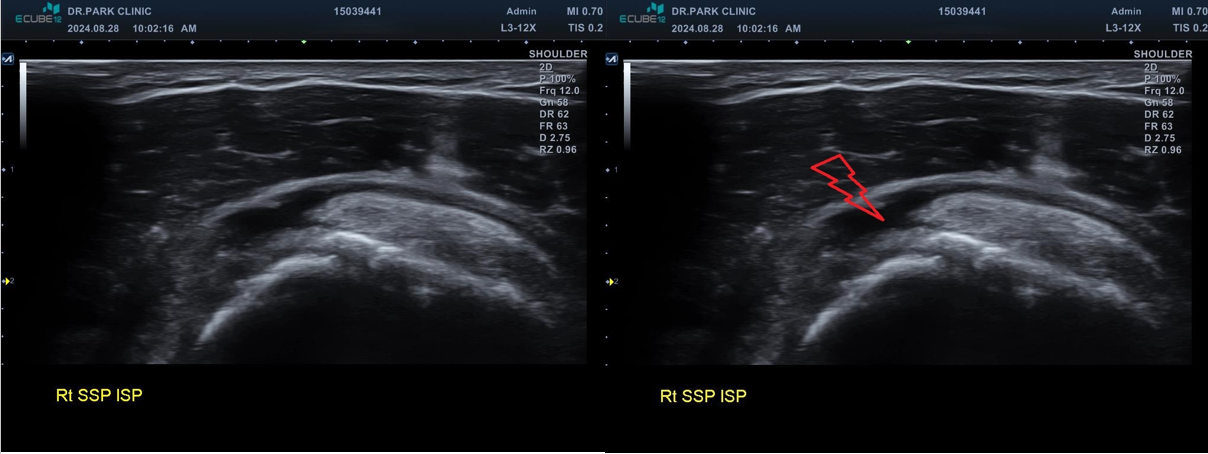

진짜 문제는 초음파 검사였는데요... 초음파 검사상에는....

마지막 초음파에서는 어깨 극상근의 파열 소견이 관찰되고 있습니다. 정확한건 mri 를 찍어봐야 하겠지만 찢어진 길이와 정도로 봐서는 수술이 필요한 극상근 전층파열로 생각이 됩니다.

나 : 초음파상에서 어깨 극상근이라는 힘줄 파열이 관찰되네요. 이게 제일 문제입니다

나 : 수술 여부는 MRI를 찍어야만 정확히 결정되는 거지만.... 초음파에서 이정도 파열인 경우 보통 수술 하는게 좋습니다.